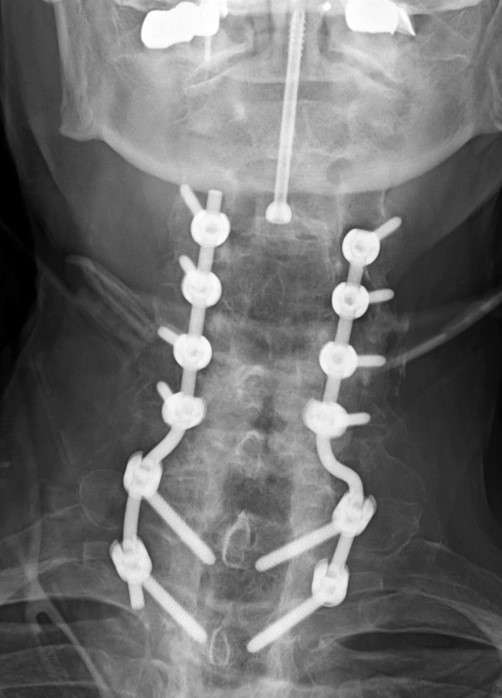

There is a hollow disk cage at C4-5 with bone chips in the cage. Posterior spinal fusion is present with lateral mass screws from C3-6 bilaterally and Pedicle screws bilaterally at T1-2 with rods running on each side from C3-T2. An anterior plate and screws is at C4-5. A laminectomy is present bilaterally through much of the cervical spine. |

| There is an unrelated posterior spinal fusion (PSF) at C3-T2 with lateral mass screws at C3-6 and pedicle screws at T1-2. |